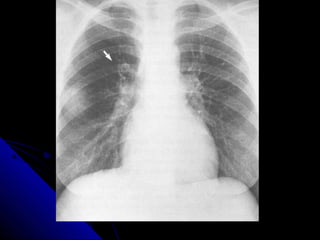

NNoodduullee//mmaassss

NNoodduulleess aanndd mmaasssseess iinn tthhee lluunngg aappppeeaarr aass

rroouunndd wwhhiittee lleessiioonnss.. IIff tthhee lleessiioonn mmeeaassuurreess lleessss

tthhaann 33 ccmm,, iitt iiss ccaalllleedd aa nnoodduullee.. IIff iitt iiss llaarrggeerr tthhaann

33 ccmm,, iitt iiss ccaalllleedd aa mmaassss..

AA nnoodduullee//mmaassss iiss ccaauusseedd bbyy eeiitthheerr aa mmaalliiggnnaanntt

((ee..gg.. lluunngg ccaanncceerr,, mmeettaassttaassiiss)) oorr bbeenniiggnn pprroocceessss

((ee..gg.. hhaammaarrttoommaa,, ggrraannuulloommaa))..

PPrriimmaarryy lluunngg ccaanncceerrss tteenndd ttoo hhaavvee iillll--ddeeffiinneedd,,

ssppiiccuullaatteedd bboorrddeerrss.. MMeettaassttaasseess tteenndd ttoo pprroodduuccee

mmuullttiippllee ssmmooootthh rroouunndd lluunngg nnoodduulleess,, oofftteenn ooff

vvaarriiaabbllee ssiizzee.. BBeenniiggnn lleessiioonnss tteenndd ttoo bbee ssmmaallll,,

wweellll ddeeffiinneedd,, ssmmooootthh,, rroouunndd aanndd mmaayybbee ccaallcciiffiieedd..